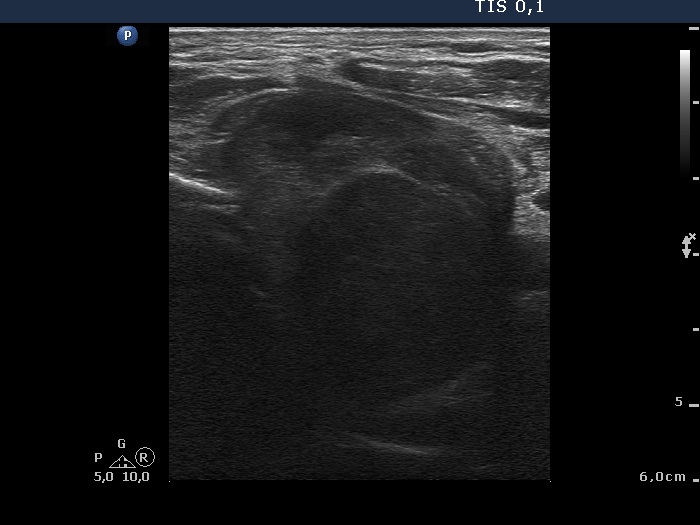

Ultrasonography revealed that the palpable mass contained the enlarged left thyroid composed of a large hypoechogenic nodule with irregular borders and multiple irregular lymph nodes in the left side of the neck.